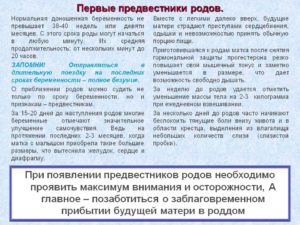

Непосредственно перед родами в организме женщины происходит множество изменений: изменяется состояние связок, мышц, меняется гормональный фон, происходят психологические процессы, которые не могут оставаться незаметными. Это и есть предвестники приближающихся родов.

Ряд симптомов, появляющихся у большинства беременных за несколько дней до родов, называют предвестниками. Их роль – обозначить готовность организма к серьезному процессу. Женский организм активно готовится к родам для того, чтобы ребенку и роженице было проще преодолеть все трудности рождения.

Предвестники родов при первых родах не всегда заметны, не регулярны и появляются в разное время. Они не дают четкого ориентира о начале процесса и не обязательно появляются все.

К окончанию третьего триместра появление предвестников не случайно. Оно связано с изменениями, происходящими с организмом беременной. Например, размягчение шейки матки влияет на характер выделений; опустившееся дно матки корректирует осанку беременной; а повышенные эстрогены влияют на аппетит, настроение и стул.

Выработка эстрогенов к 39неделе существенно увеличивается, а уровень прогестерона, который все 9 месяцев блокировал сокращения матки, падает. Активизируются простагландины, стимулирующие начало родовой деятельности.

- Опускается живот (если это не случилось ранее). У впервые рожающих женщин этот предвестник заметнее, чем у тех, кому предстоят повторные роды. Это связано с большей эластичностью мышц живота. За положение живота отвечают мышцы передней брюшной стенки.

У женщин, которые готовятся к повторным родам, мышцы заметно слабее, поэтому их живот опускается за день-два до родоразрешения. При «опускании» на 2-3 см меняется высота дна матки. Это происходит, потому что нижняя часть матки перед родами становится эластичнее, ребенок плотнее прижимается к костям малого таза и готовится «на выход».

В связи с этим заметной становится смена формы живота и его положения относительно груди – он приобретает не острую, а каплевидную, покатую форму. Заметить это можно по тому, что освобождается диафрагма, а между грудью и животом можно положить ладонь. Становится проще дышать, но нарастает давление на промежность и нижнюю часть тела.

- Выход пробки. Если вы наблюдаете этот предвестник, значит шеечная слизь начала разжижаться и вытекать. Всю беременность густая пробка не позволяла инородным бактериям проникать к ребенку. Если пробка появилась, значит, гормоны делают свое дело, разжижая ее и готовя шейку к растяжению. Перед родами растет уровень эстрогенов, обычно это происходит за 2-7 дней до родов. В норме пробка может выходить несколько дней. Изменяющийся гормональный фон увеличивает слизистые выделения и из полостей носа. Влагалищные выделения имеют водянистую фактуру и бежево-коричневатый цвет, могут содержать небольшие прожилки крови. Не путайте слизь пробки с подтеканием околоплодных вод. Они подтекают не одномоментно, а постоянно, причем объем увеличивается при напряжении мышц пресса. Воды светлые, розоватые или зеленоватые. При обнаружении вод, нужно срочно показаться гинекологу, в то время как за выходом пробки можно спокойно наблюдать дома.

- Уменьшение массы тела. Это происходит буквально за 2-3 дня до родов. Потери веса могут достигать 3 кг. Организм освобождается от лишней жидкости, выводя ее с мочой. Особенно заметна потеря веса, если у беременной наблюдались отеки. Этот предвестник возникает в связи с тем, что организм готовится минимизировать кровопотерю при родах, если она случится. Механизм таков: снижается объем жидкостной составляющей крови. Таким образом организм делает кровь гуще, повышая показатели ее свертываемости: вероятная кровопотеря при родах будет меньше. Вторая причина выведения лишней жидкости – это отсутствие расхода на генез амниотической жидкости. Не требуется больше и наращивать объем крови для работы в системе мама-ребенок. Случается, что перед родами организм избавляется от жидкости не только с мочой, но и с жидким стулом.

- Самый яркий предвестник родов – это тренировочные схватки. Матка пробует себя, готовится к родовой деятельности. Предвестниковые сокращения аритмичны. Могут длиться несколько недель и, как и сокращения Брекстона-Хикса, призваны подготавливать матку к работе во время родов. Подобные тренировки помогают созреванию шейки матки, расширяя и укорачивая ее. До 37 недели схватки не являются предвестниковыми. Не путайте тренировочные схватки с тонусом матки и настоящими родовыми схватками. Различия существенны, хотя возникают все эти сократительные активности по одному принципу: мышцы матки напрягаются, становясь плотными, четко очерчивают ее контур, возникает тяжесть в области крестца и внизу живота. Предвестниковые схватки короткие и относительно безболезненные. Наблюдаются до 6 раз в сутки, способствуют активизации кровообращения и обеспечивают ребенку доставку большего объема питательных веществ. Тренировочные сокращения проходят сами или смягчаются при приеме дротаверина или постановке расслабляющей свечки, при массаже, принятии душа. Тонус матки – это длительное, болезненное, не проходящее напряжение, угрожающее плоду. Родовые схватки, в отличие от тренировочных, регулярны, их интенсивность и частота нарастают. От них невозможно отвлечься.

- О степени созревания шейки матки рассказать может только акушер. Во время беременности длина шейки – 3 см. Пред родами она уменьшается до сантиметра-полутора. В родах шейка, представляющая собой мышечную трубку, должна окончательно растянуться и раскрыться. Короткая шейка – признак скорых родов. Длинная шейка на 39 неделе считается незрелой. О состоянии шейки судят на основе влагалищного исследования: зрелая шейка расположена в центре, легко растягивается, мягкая, с проходимым цервикальным каналом.

- В целом, при сочетании нескольких видов предвестников с нарушением аппетита, возникновением расстройства кишечника, можно говорить о близости родов.

Появление предвестников вовсе не означает, что наступили роды. Иногда предвестники могут длиться 2-3 недели. Длина беременности зависит от характера менструального цикла женщины. Вероятность рождения малыша на 39 неделе наиболее велика у женщин, с промежутком между менструациями в 21 день.

Классическое начало родов для первородящих – это не сочетание предвестников, а только регулярные схватки, нарастающие со временем. При нормальной беременности ехать в роддом нужно при 10-минутном перерыве между маточными сокращениями.

Рожавшим женщинам поездку в роддом нужно планировать чуть раньше. В силу анатомических особенностей шейка их матки обладает более широким просветом, а также сильнее отзывается на гормональную стимуляцию.

Предвестники у повторнородящих выражены сильнее и замечают их раньше. К примеру, больше жидких выделений, объемнее пробка, повторнорожающих женщин сильнее беспокоят пробные сокращения.

Отмечается также, что роды могут быть быстрее, чем в первый раз, а предвестники наступают всего за сутки-двое до родоразрешения.